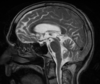

63 anos, Mulher, Hiponatremia corrigida, Hipotireoidismo.

Sindrome de desmielinização osmótica Mielinolise extrapontina (20% dos casos)

Qual o padrão da Mielinolise pontina e extrapontina?

Local: Ponte isolada (50%); Ponte + extraponte (30%) e extrapontina isolada (20%); Achado: Hiperintensidade central T2 na ponte, poupando os tratos corticoespinais dando aspecto de sinal do tridente; restrição a difusão é o mais precoce achado; Localizações extrapontinas: núcleos da base; mesencéfalo e substância branca;

316